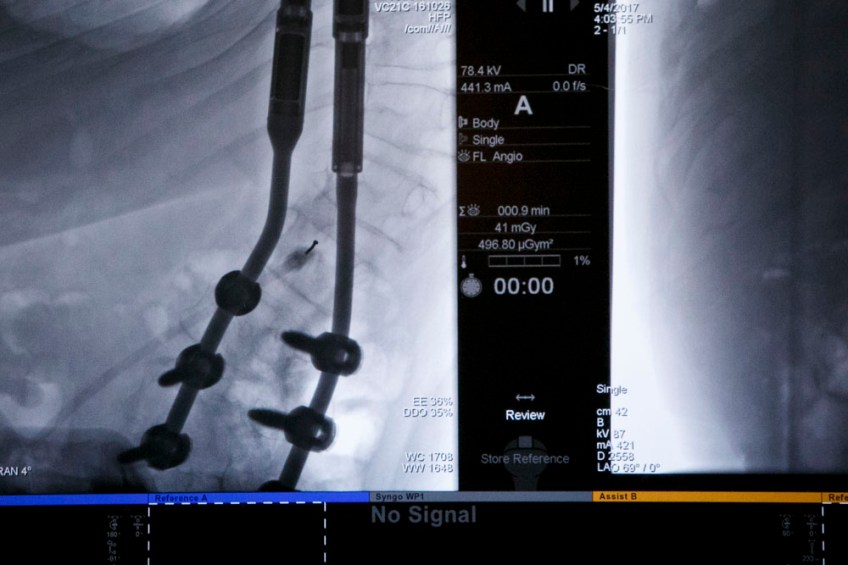

Spinraza treatment Published January 4, 2019 at 1000 × 667 in Spinraza treatment Special imaging technology in a “neurointerventional” surgery suite at Norfolk General allows doctors to see a clear path to where Spinraza is injected into the spine of Jackson Saville on Friday, May 5, 2017.